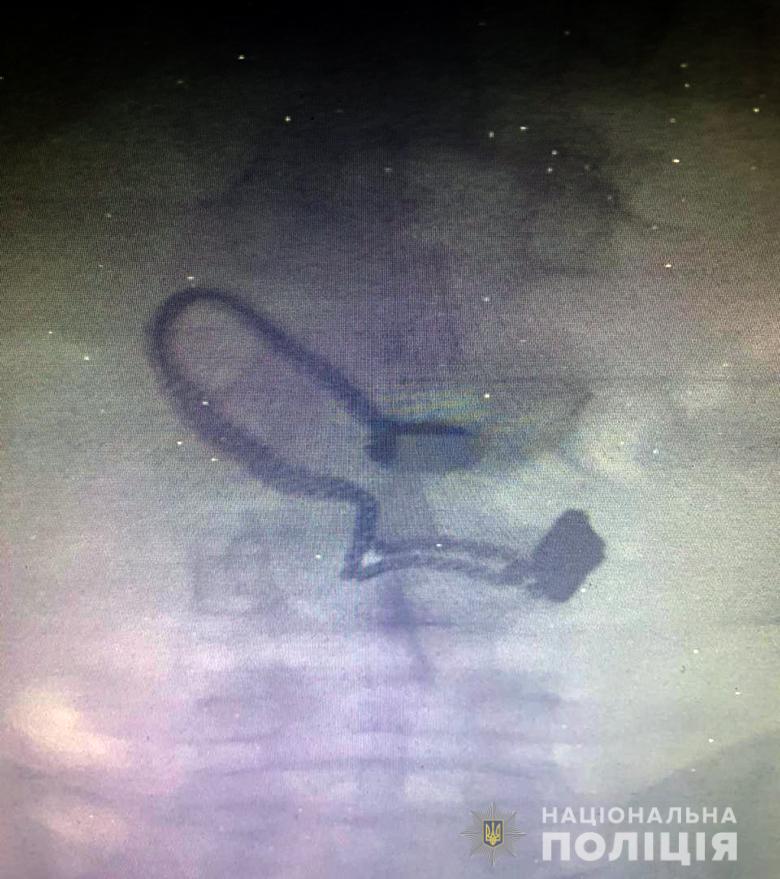

Грабителем оказался 26-летний житель Луганской области, ранее уже судимый за кражи. Его задержали. Во время поверхностного осмотра у мужчины нашли кошелек потерпевшей. Позже он признался полицейским, что сорванную цепочку проглотил.

"Во время медосмотра на рентген-снимке задержанного врачи обнаружили украшение", - сообщают в полиции.